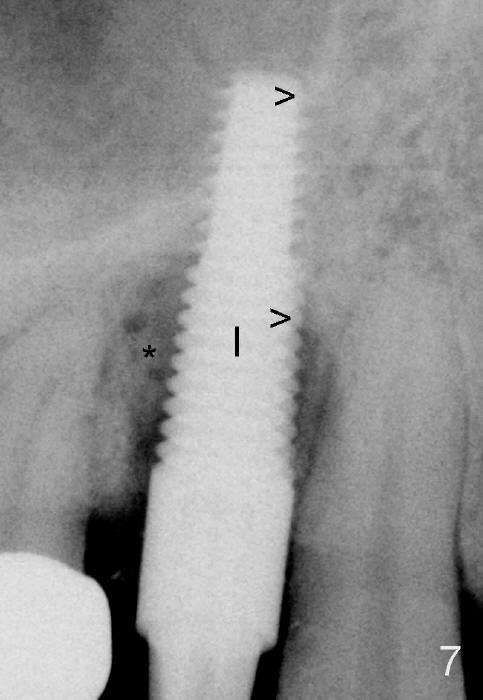

In spite of large periapical radiolucency (Fig.1 *), osteotomy is easier than expected. Use 2 mm pilot drill, 2.5-3.5 mm reamers from 14 mm (bottom of the socket) to 17 mm (sinus floor). The initial point for osteotomy at the bottom of the socket is easy to establish, because it is flat. By the time 5x20 mm tap is inserted, it is palatal (Fig.5). It is mandatory because the buccal plate has been perforated. The tap has to be inserted deeper (from 17 mm to 20 mm, Fig.6) to achieve stability. Insertion torque of 5x20 mm implant (Fig.7 I) is > 60 Ncm. The implant remains palatal so that there is space for bone graft (Fig.8 *). But the bone graft is a little over packed; there is no room to place collagen dressing. The latter will be dislodged and bone graft will be lost if perio dressing is loose prematurely. The perio dressing may have to be re-applied. Depth of bone graft is deemed sufficient if the implant threads are covered. Maximum will be on the rough surface. Physiologically, bone does not extend to the gingival margin.